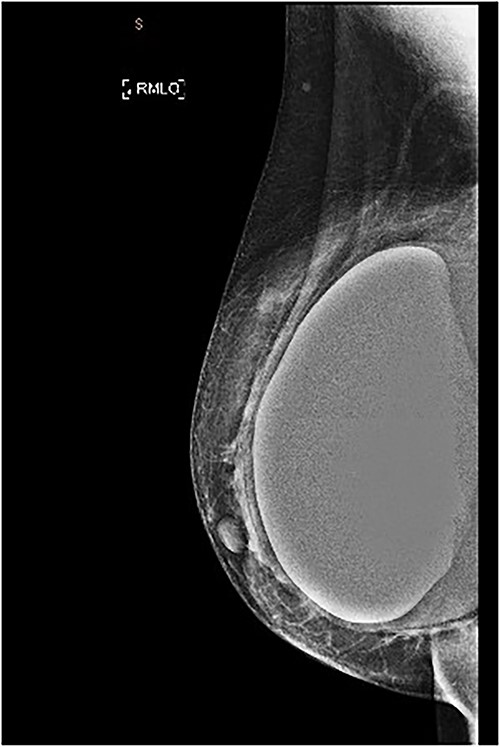

She underwent bilateral mammograms and ultrasounds of breasts and axillae (Figs 2, 3A and 3B). Within the right breast, the mammogram demonstrated a suspicious mass with two calcified foci that correlated to a 19 × 15 × 6-mm hypoechoic lesion at the 9/1 o’clock position on ultrasound. Core biopsy confirmed this to be a Grade 2 invasive ductal cancer (IDC), which was ER/PR positive and HER2 negative.

MMG of the right breast in MLO view showing a lesion in the upper breast.